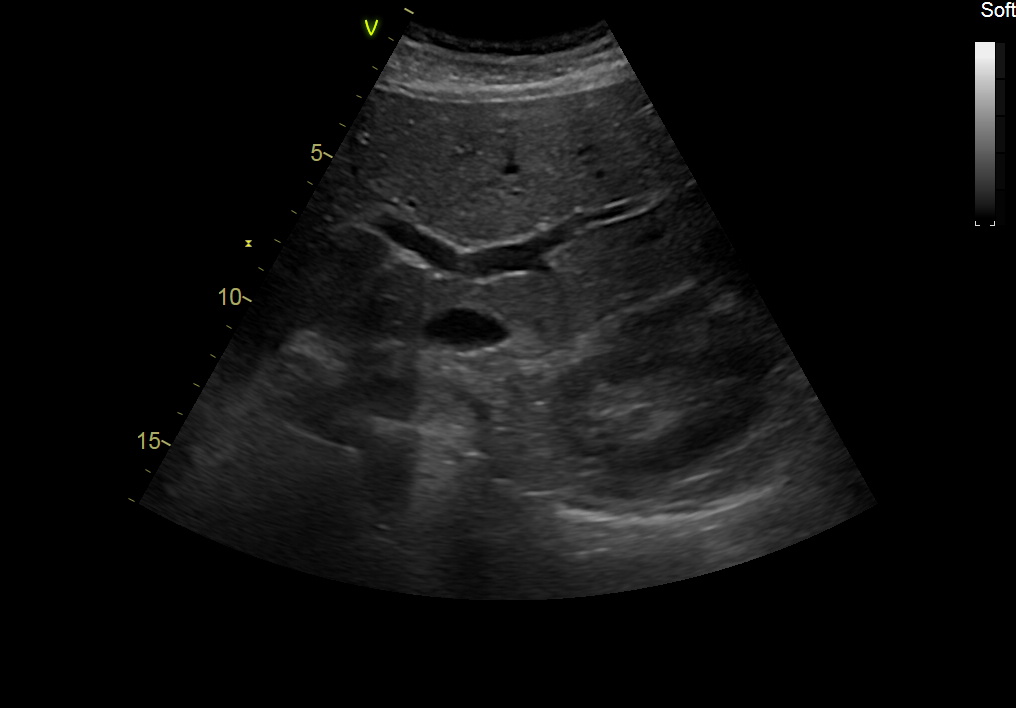

GE C1-6-D Abdominal Convex Refurbished

GE Convex C1-6-D Abdominal

Intended use

Abdominal and Women’s Health

Frequency Range

6 – 1 MHz

GE C1-6-D Abdominal Convex

Frequency Range: 6 – 1 MHz

GE C1-6-D Abdominal Convex for Abdominal and Women’s Health